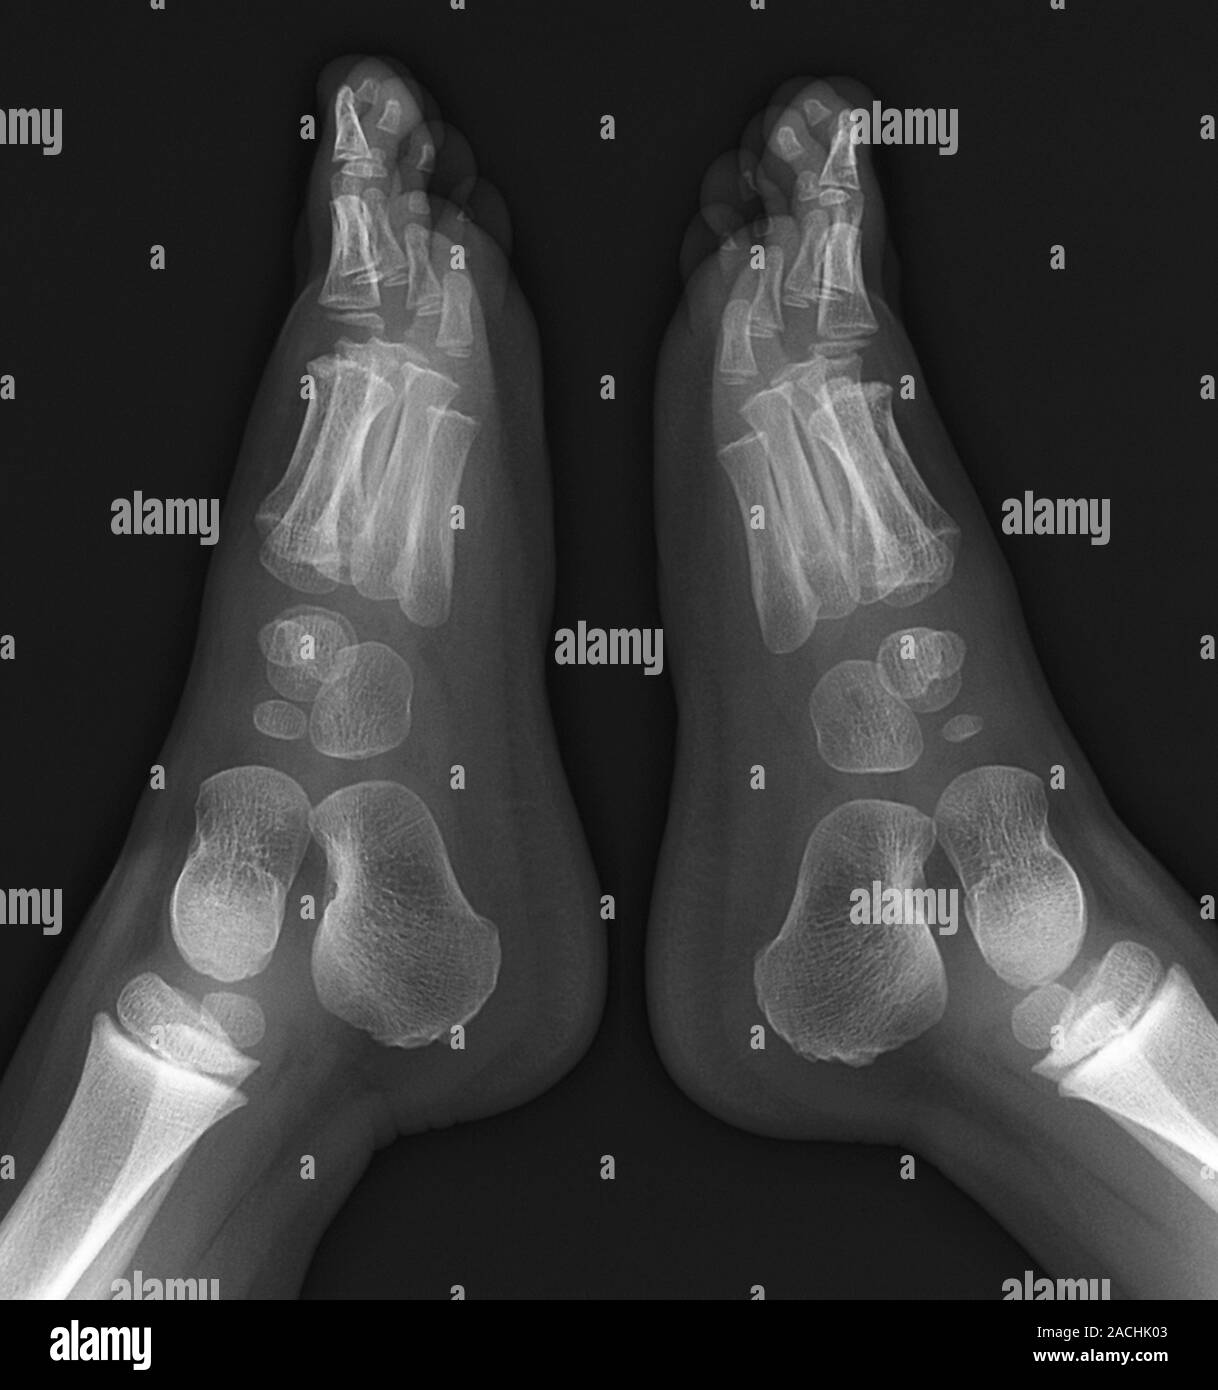

Xray Image, Both Foot AP View, Show Normal Pediatric Bone. Stock Photo Child's Foot X Ray clinical scenarios are included to orient the learner to the evaluation of pediatric foot alignment. in this article, we review common injuries and unusual disorders of a child’s foot and include a discussion on. It is useful in diagnosing fractures, soft tissue effusions, joint. This projection demonstrates the foot joint in its natural anatomical position. tips for. Child's Foot X Ray.